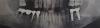

7542 Опубликовано 24 июля, 2013 Поделиться Опубликовано 24 июля, 2013 У меня за много лет выдвинулись вверх 4 и 5 зубы на нижней челюсти, и сейчас нужно их (или только 5) обтачивать или просто так, или под коронку. Вопрос возник в связи с тем что уже 1,5 года как установлены импланты на верхней челюсти и пора бы туда поставить коронки. Вот я в раздумьях, или забить на импланты (верхние 4,5) пусть про запас стоят когда-нибудь понадобятся и не трогать нижние т.к. они не леченые никогда, или пилить их ради того чтобы вверху был полный ряд. А что если есть какие-то способы задвинуть эти зубы на место ? Сколько это стоит примерно (Москва) ? Я знаю что крупные жевательные задвигают резинками на мини-имплантах, а как обстоят дела с нижними 4 и 5 ? P/S/ прошу прощения что в 3 раз закачиваю фотку на сайт уважаемого Док-а но не нашел способа как использовать одно фото в разных темах. Ссылка на комментарий

Премоляр Опубликовано 24 июля, 2013 Поделиться Опубликовано 24 июля, 2013 (изменено) С нижними 4,5 надо что то делать,оставлять так нельзя. Вариант с интрузией на микроимплантах можно рассмотреть. Разумеется,потом импланты и протезирование антагонистов( верхние). Но места для двух имплантов сверху недостаточно,надо создавать. Импланты с коронками слева снизу не подвижны? Изменено 24 июля, 2013 пользователем Премоляр Ссылка на комментарий

7542 Опубликовано 24 июля, 2013 Автор Поделиться Опубликовано 24 июля, 2013 (изменено) Вроде бы нет, я как-то не задумывался над этим. Жую себе и жую. Специально расшатывать не хочу. Они были установлены в 2008, приживались год пока решался вопрос с антагонистами и получили нагрузку в 2009 году, получается им 5 лет и 4 года работают. Я обратил внимание в 2011 на потемнение вокруг импланта 6 , он в сравнении с 7 выглядит как будто болтающимся в воздухе что и заметно на фото, Но второй доктор который ставил импланты на верхнюю челюсть, ничего плохого не сказал конкретно по этому снимку про нижние импланты, я его спрашивал как там они. Когда доктор-1 вкручивал в 2008 нижние импланты, я обратил внимание что один из них закручивался туго и явно капитально, а второй как-то без должного усилия. У некоторых пациентов на снимках здесь тоже вижу темное пространство вокруг имплантов, т.е. плотность кости получается низкая и рентгеновское излучение проходит свободно. Это может быть просто свойствами кости (более высокая "прозрачность" для рентгена) при сохранении механических свойств ? Или это однозначно признаки оторжения или неприживления ? Возможно я не замечаю проблем потому что там мост на 2 импланта и он работает даже если второй будет плохо сидеть в кости ? Про верхнюю часть вы прям меня расстроили... это я о том что там мало места. Мне же туда уже 2 импланта закрутили, потом по снимку доктор сказал что на его взгляд нормально получилось, вот только снимка того у меня нет, и коронки на эти импланты давно пора ставить а я тупить начал потому что жалко стало исправный зуб пилить под коронку, я когда верхние импланты ставил (4 штуки) в принципе понимал что возможно они будут так, про запас. Потому что с одной стороны надо пилить нижний здоровый и не хочется этого, а с другой стороны уже чуток болтался мост на 4 зуба и я понимал что при снятии слепков для коронок на верхние импланты он может не просто слететь а как рычаг выломать мне нижние 4 и 5, а идти к доктору-2 и требовать чтобы этого не произошло, как-то нелогично. Теперь нижний мост на 4 зуба отвалился малой кровью, и с той стороны я уже получил совет что 7-ка под щипцы однозначно, с той стороны есть определенность а вот с другой стороной возможны варианты... Может я глупость скажу, но есть ли возможность использовать при задвигании нижней 5 уже более года как установленные верхние импланты ? Возможно какие- то резинки типа ластика туда прикручивают, которые начинают понемногу и мягко надавливать на нижний зуб и его принуждать к возвращению на место ? Изменено 24 июля, 2013 пользователем 7542 Ссылка на комментарий

Премоляр Опубликовано 25 июля, 2013 Поделиться Опубликовано 25 июля, 2013 Ваш снимок малоинформативен. Сложно планировать лечение,точнее невозможно. Ссылка на комментарий